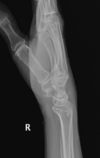

Fratura de Chaffeur

Fratura do processo estilóide do rádio.